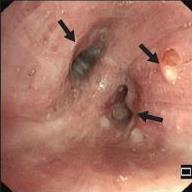

• 侵袭性肺真菌病的支气管镜表现及介入治疗效果

2025, 31(9):81-90. DOI: 10.12235/E20250317

摘要 (112) HTML (56) PDF 6.06 M (77) 评论 (0) 收藏

摘要:目的 探讨侵袭性肺真菌病(IPFD)的支气管镜表现,并评估介入治疗的安全性和疗效。方法 回顾性分析2018年5月12日-2025年5月12日于该院行支气管镜检查的35例IPFD患者的临床资料,观察IPFD的支气管镜表现及介入治疗效果。结果 共收集35例患者临床资料。其中,男22例,女13例,患者年龄(53±14)岁。基础疾病包括:血液系统恶性肿瘤10例,长期应用糖皮质激素者5例,2型糖尿病者4例,肺部恶性肿瘤2例,器官移植1例。胸部CT显示:肺部病变累及单肺叶者19例,累及多肺叶者16例。支气管镜下表现主要为:黏膜充血水肿29例(82.9%)、坏死物堵塞管腔22例(62.9%)、大量黏稠脓性分泌物17例(48.6%)、支气管部分狭窄或闭塞16例(45.7%)、黏膜坏死9例(25.7%)、黏膜出血5例(14.3%)、真菌球3例(8.6%)。其中,32例(91.4%)接受全身性抗真菌治疗,17例(48.6%)接受支气管镜局部两性霉素B灌注治疗,10例(28.6%)采用活检钳钳除病灶,6例(17.1%)采用冷冻探头冻取病灶,4例(11.4%)接受氩气刀治疗。28例(80.0%)临床症状明显改善,肺部影像学病灶缩小或消退;4例(11.4%)病灶稳定;3例(8.6%)未完成治疗。结论 IPFD多见于免疫抑制宿主,支气管镜常表现为:坏死物堵塞管腔、伴脓性分泌物、支气管管腔狭窄和局部黏膜充血水肿或坏死。全身抗真菌药物联合支气管镜下介入治疗,安全性高,且疗效好。